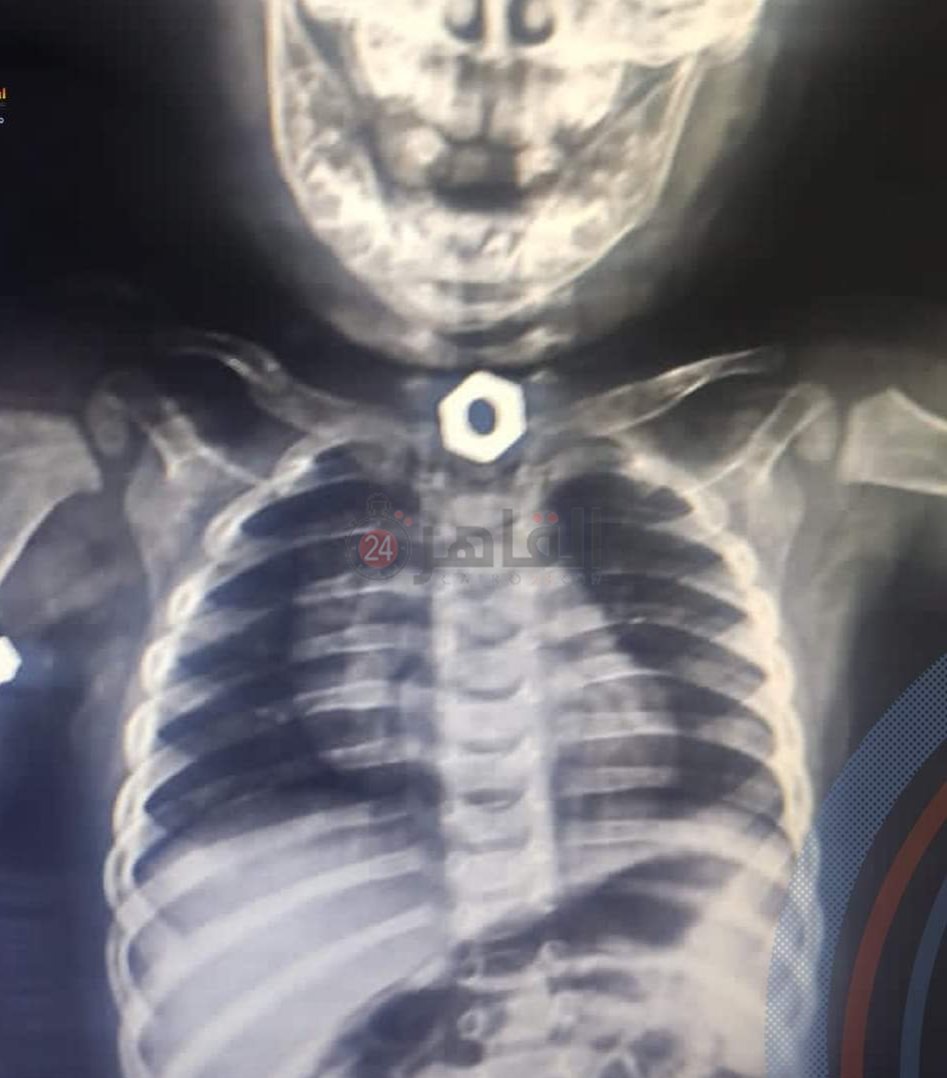

نجح فريق طبي بأحد مستشفيات مدينة الغردقة، في استخراج جسم معدني من معدة طفل يبلغ من العمر 8 أشهر.

وقال الدكتور رضا النجار رئيس مجلس إدارة المستشفى، إن قسم الجراحة والمناظير بالمستشفى نجح في استخراج جسم معدني صامولة من معدة طفل رضيع يبلغ من العمر 8 أشهر عن طريق منظار المعدة تحت مخدر كلي.

وأضاف النجار في تصريح خاص لـ القاهرة 24، أن عملية استخراج جسم غريب من طفل في هذه المرحلة العمرية تتم للمرة الأولى داخل مستشفيات البحر الأحمر، حيث قام بإجراء المنظار الدكتور محمود إدريس استشاري الجراحة والمناظير، وقام بتخدير الطفل الدكتور إبرام ممدوح استشاري التخدير.